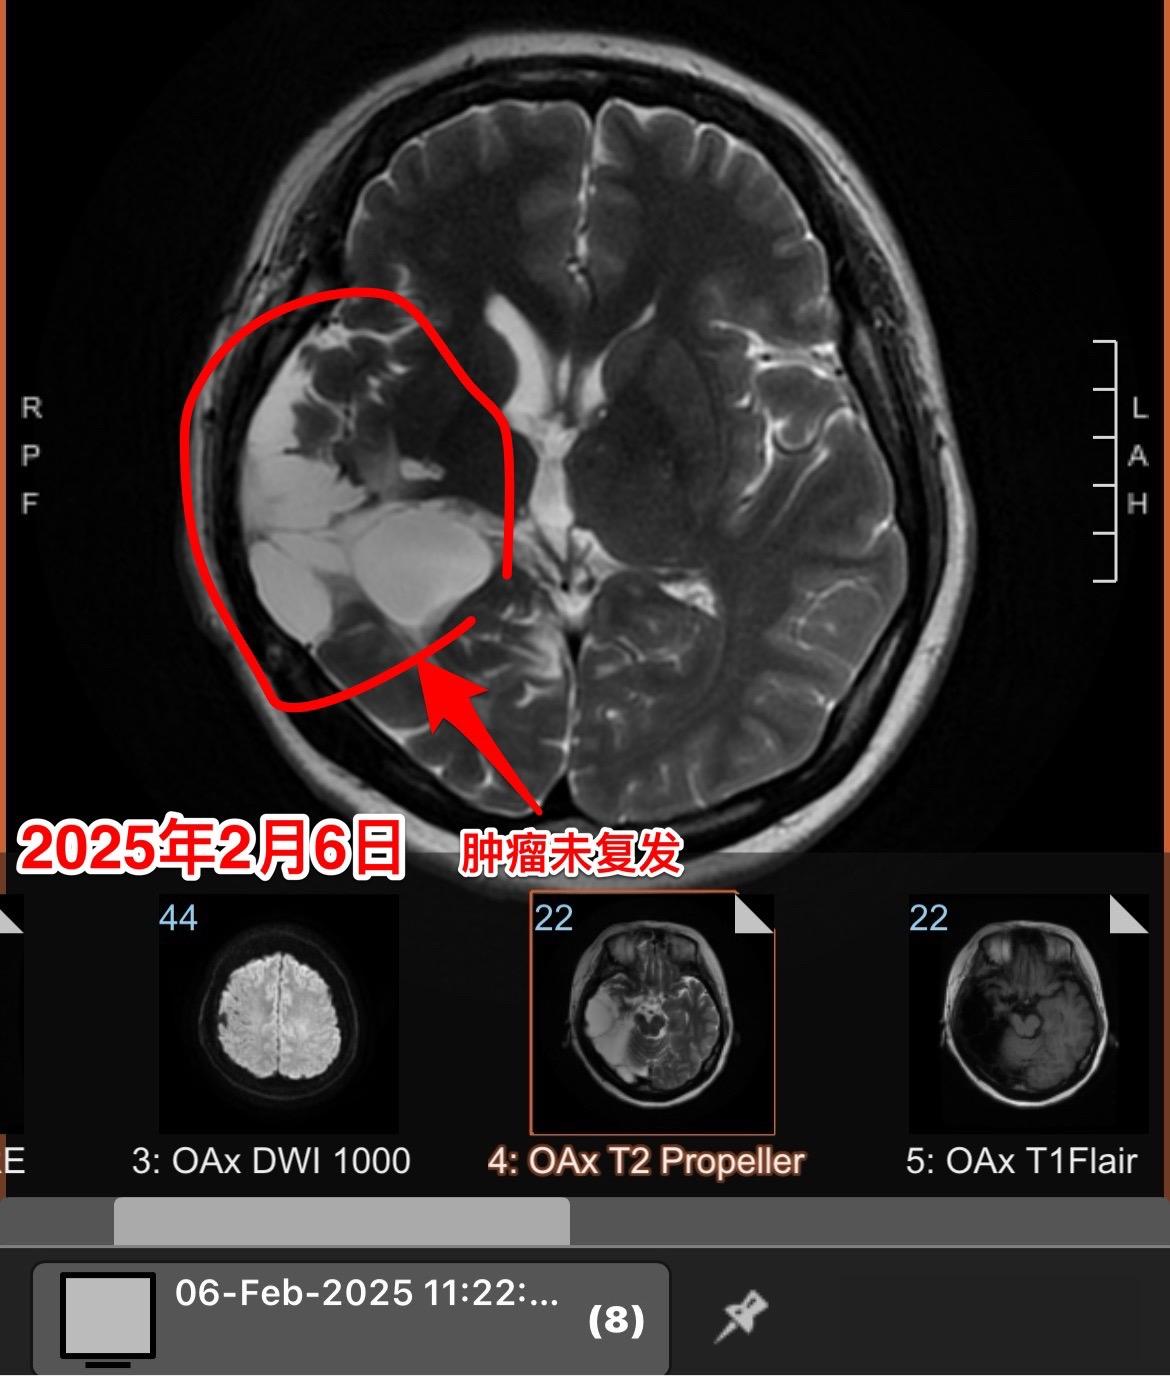

高级别胶质瘤要争取完全切除。新年上班第二天,今天收到一个胶质瘤病人手术后近5年复查的磁共振结果。 当时40岁的海城市女性于2020年5月因头痛发现脑部胶质瘤。于2020年5月15日在我科行手术切除肿瘤。 手术后病理报告为间变少突胶质瘤,没有找到合适的化疗药,出院后患者只作了脑部放疗,定期复查。 今天的磁共振显示肿瘤没有复发,太棒了👏